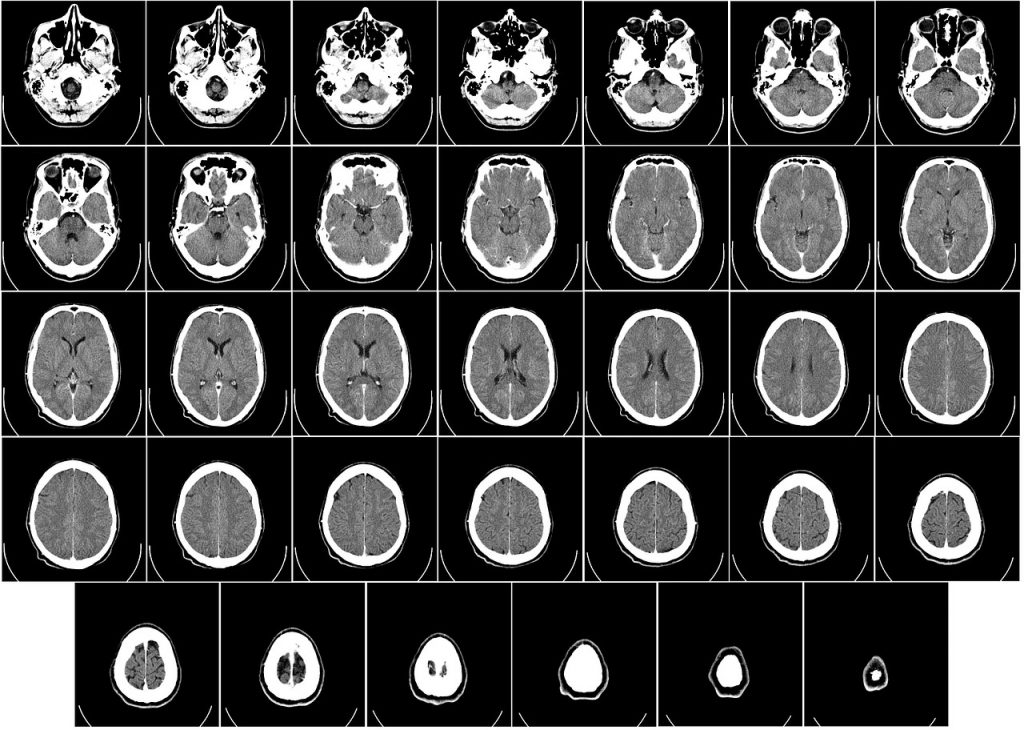

Con motivo del Día Mundial de la Esclerosis Múltiple, que se celebra el 30 de mayo, la neuróloga precisa que es un problema de salud del sistema nervioso que afecta al cerebro y la médula espinal, lesionando el material que protege las células nerviosas.